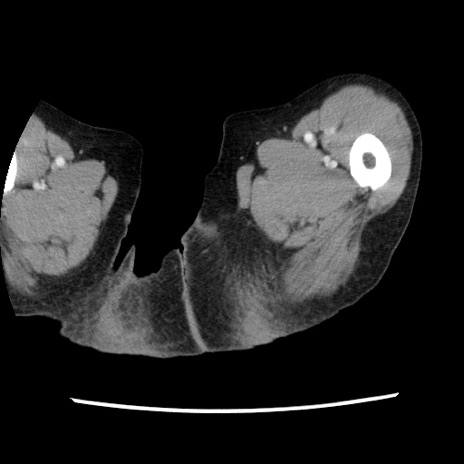

症例1(横断像)

症例

【症例】80歳代女性

【主訴】腹痛

【現病歴】8時間前から腹痛あり来院。

【既往歴】糖尿病、脂質異常症、子宮体癌にて子宮全摘術

【身体所見】意識清明・会話良好だが腹痛で苦悶様、全腹部にわたって反跳痛と圧痛あり

【データ】WBC 13600、CRP 0.14、LDH 224、CK 90